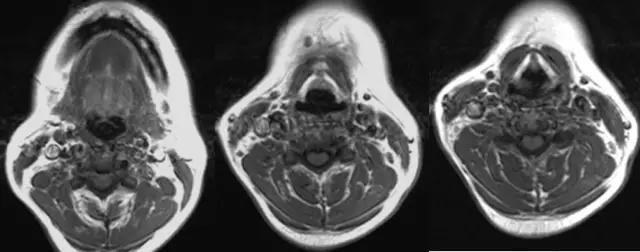

3、MRI

- 采用颈部线圈,下颌上抬,垫高肩部以抬高喉部;

- 横断面扫描与声带平行,扫描范围自会厌上缘至环状软骨下缘,层厚3-5mm;

- 冠状面显示声带、室带、喉室、胸廓入口等情况较好;

- 矢状面显示舌根、会厌、会厌前间隙、声带前联合较好;

- 检查时病人喉部放松,平静呼吸,尽量减少吞咽动作以减少伪影。

2、CT、MRI检查

喉软骨:软骨骨化及髓腔形成的程度。

1、年轻人软骨未骨化,T1及T2WI等信号,CT等密度,与其它软组织较难区分。

2、30岁以上成年人T1WI中央高信号代表脂肪及黄骨髓生成。年老时骨化变为皮质骨,信号减低。CT为高密度。

3、会厌软骨由弹性软骨组成,T1WI略低于肌肉,T2WI略高于肌肉。CT呈等密度,少有钙化。